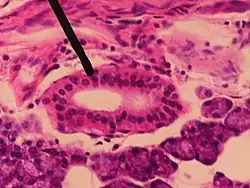

Section of submaxillary gland of kitten. Duct semidiagrammatic. X 200.